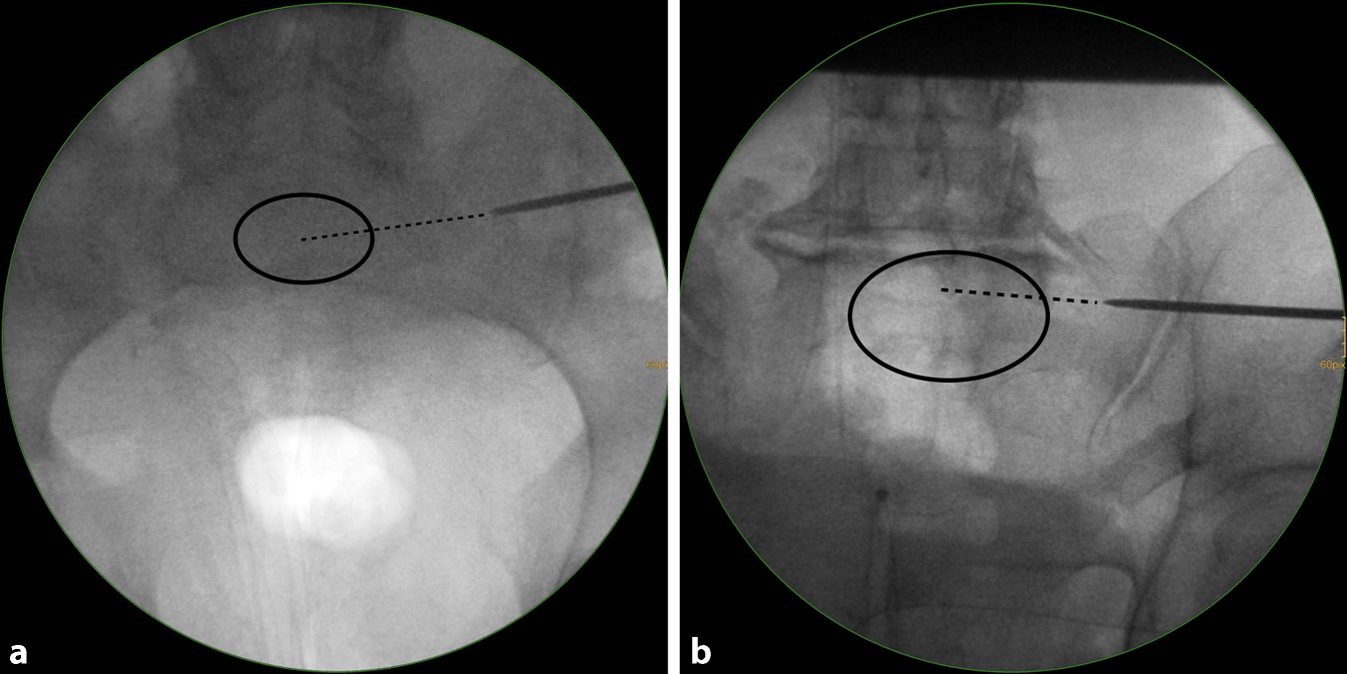

Fig. 6

Fluoroscopic control in the inlet and outlet view. The wire trajectory is first controlled in an inlet view (a). It targets the central part of S1 (dotted line) and is therefore considered as safe. A more anteriorly directed trajectory would have been safe as well according to the preoperative planning (MC—MA). b The wire trajectory is then controlled in an outlet view. It follows the MC—UC trajectory, which is safe according to the preoperative planning (MC—UC). U upper, M middle, L lower, A anterior, C central